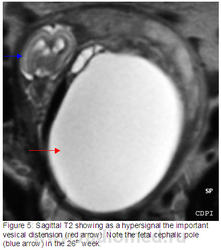

Рисунок 1: